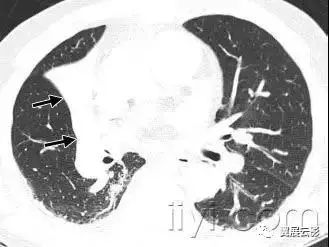

十一、支气管扩张

病理:是不可逆性的局限或弥漫性支气管扩张,通常是慢性感染、近端气道梗阻或者先天性支气管异常造成的。

平片和CT:薄层CT上的形态学标准为:与临近的血管相比,支气管扩张呈印戒征,支气管逐渐变细的形态消失。胸膜下25px内可见气管分支。根据受累气管的形状,支气管扩张可以分为管状、蔓状或囊状。经常伴随关闭的增厚、粘液嵌塞和小气道的异常。